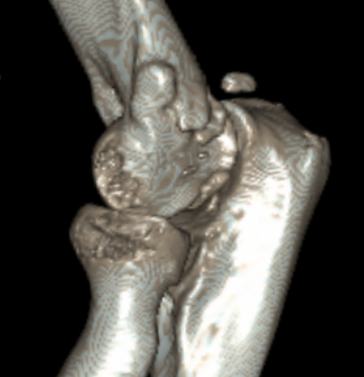

Multiple elbow loose bodies

Single loose body in adolescent

Capitellar OCD www.boneschool.com/capitellar-OCD

Elbow osteoarthritis and & stiffness www.boneschool.com/elbow-OA